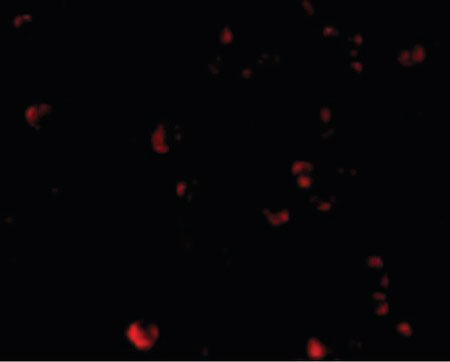

Immunofluorescence of TDP43 in HeLa cells with TDP43 antibody at 20 ug/ml.